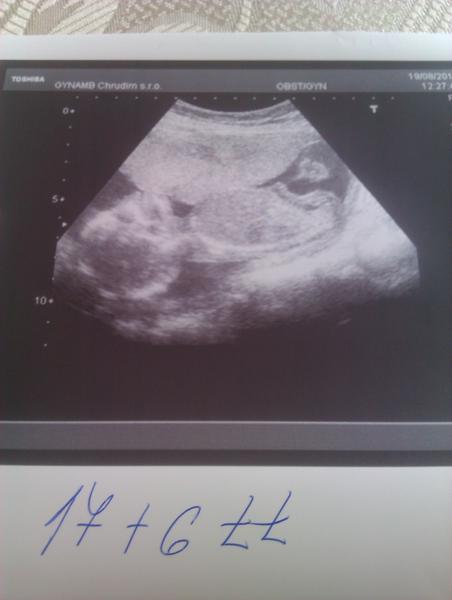

Ahojj kocky,tak jsem vcera mrkla na Sanus,Vodicka dostal foto z utz a videla jsem nejkrasnejsiho pindika..takze kluk jak buk.kavove zrnko to rozhodne nebylo.ja kluka citim a jsem stastna,ze se potvrdil.jinak jsme ok,jen mlade je akcni,ze nemam foto.pohyby v plnem proudu.